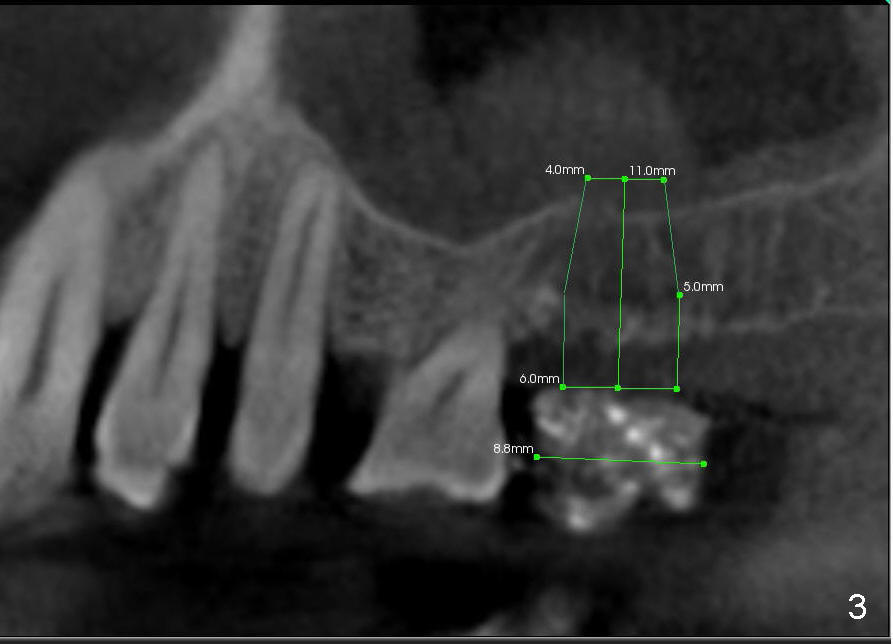

The method of sinus lift depends upon bone density.  A brief look at the CT scan reveals that bonedensity is high (H, Fig.1) in the dentulous area  (1st molar), medium (M) in the tuberosity and low (L) in the edentulous area (2nd molar).  The lower right of every CT planar image shows Hounsfield unit of a particular area where the mouse curse rests.  The map of bone density is shown in Fig.2.

The density of the medullar area of the edentulous is so low (10) that the sinus floor (bone density 300) has to be used for primary stability of the implant.  Additionally, an osteotome may encounter resistance when it penetrates the crest (bone density 200; a cortical plate).  Once past the crest, tapping the osteotome through the cancellous bone should be easy until reaching the sinus floor (cortex).